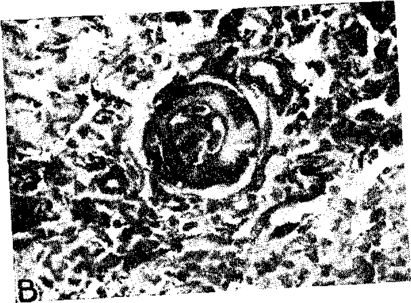

У всех собак, проживших после двустороннего удаления почек в течение 6 - 9 недель, имело место постепенное повышение кровяного давления, которое достигало 200 мм ртутного столба. При гистологическом исследовании кроме острых изменений в мелких сосудах (плазматическое пропитывание, очаговые некрозы, кровоизлияния), наблюдался гиалиноз их стенок со значительным сужением просвета (рис. 20); интима подвергалась значительному утолщению, что напоминало картину эид-артериита. Нередко имели место значительные дистрофические изменения в средней оболочке аорты (Муирхед, Турнер, Грольман, 1951).